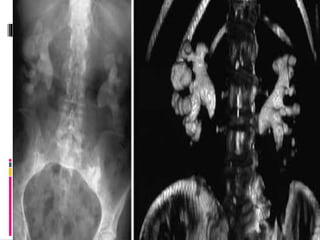

 CT Scan : Helpful to diagnose Radiolucent Stones & determining stone densityThe

imaging of choice in patients with renal colic No contrast complications No need to

asses kidney function before use May show other causes of acute abdominal pain It

can predict stone fragility.

Investigations

Left Renal Stone - Axial Right Renal Stone - Coronal

Right Renal Stone – 3D Reconstructive